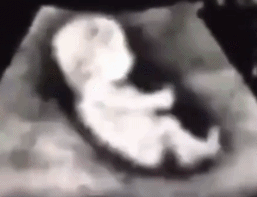

是不是很多妈妈们也都好奇呢?小宝宝在妈妈的肚子里要待10个月了 , 一个人在子宫这个小房子里 , 每天现在干什么呢?除了睡以外 , 还能做些什么呢?会不会很无聊啊?

之前在新闻里看到的这样一个画面 , 我也很好奇这是不是PS的呢: